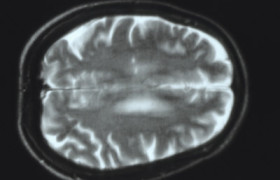

Рассеянный склероз является хроническим аутоиммунным заболеванием, при котором происходит разрушение белого вещества головного и спинного мозга. На данный момент не существует таких препаратов, которые могли бы бороться с рассеянным склерозом, так же как нет и ни одного зафиксированого случая избавления от данного...